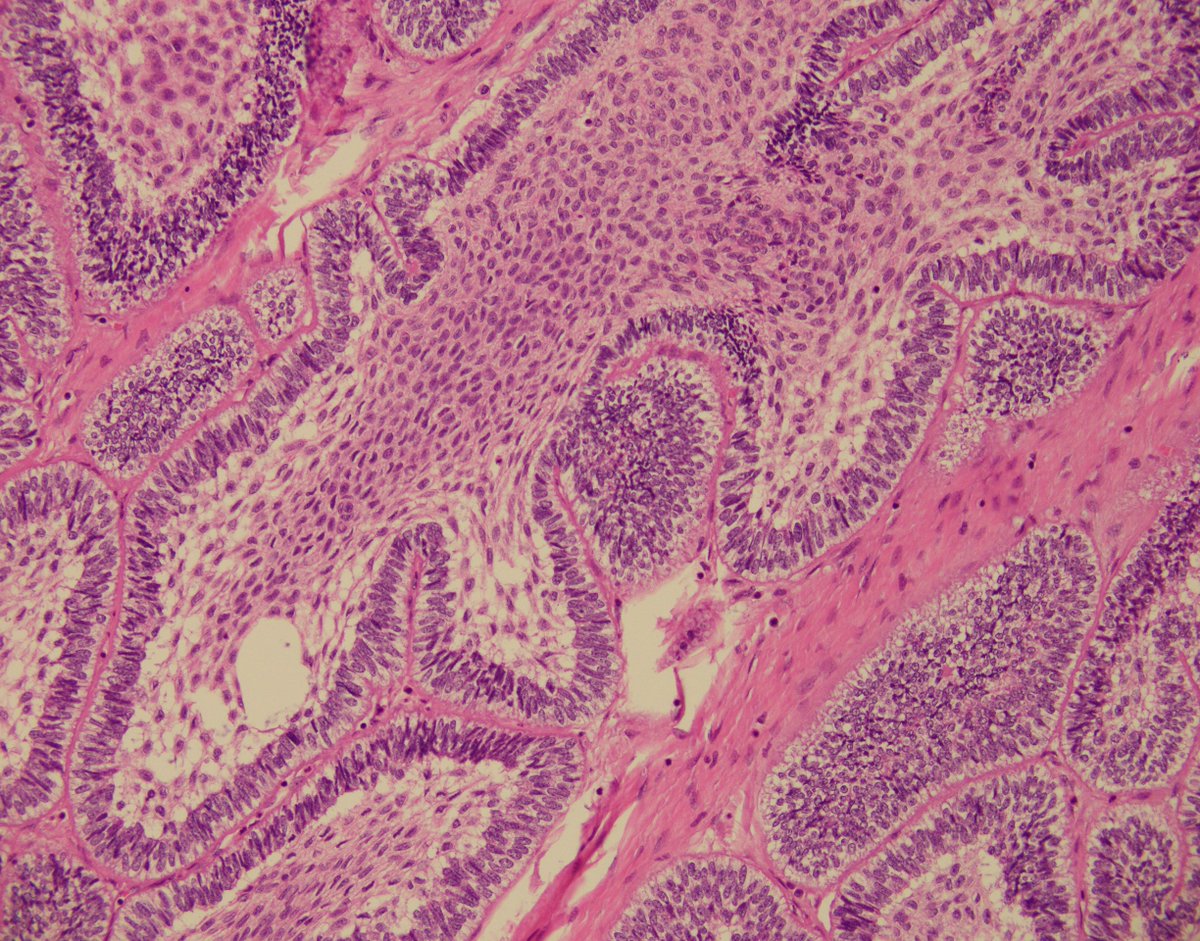

Cristina Magi-Galluzzi, M.D., Ph.D., Robert and Ruth Anderson Endowed Chair in Pathology, was installed as the 2026-2027 president of USCAP - United States and Canadian Academy of Pathology @TheUSCAP, effective April 1, 2026. Congratulations, Dr. Magi! 💚 bit.ly/4sgU4D1